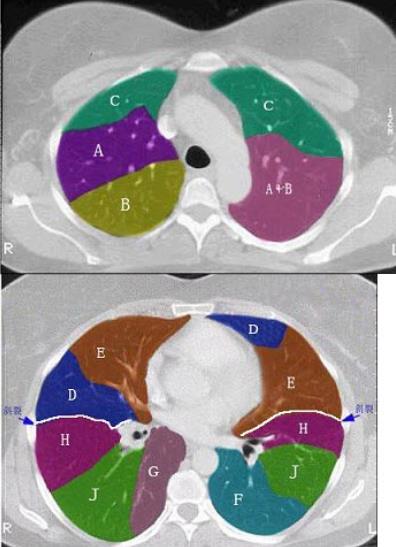

- 单项选择题 结合肺段模式图,选出右肺下叶的组成()。

A、F

B、F+G

C、F+G+H

D、F+G+H+I

E、F+G+H+I+J

- E